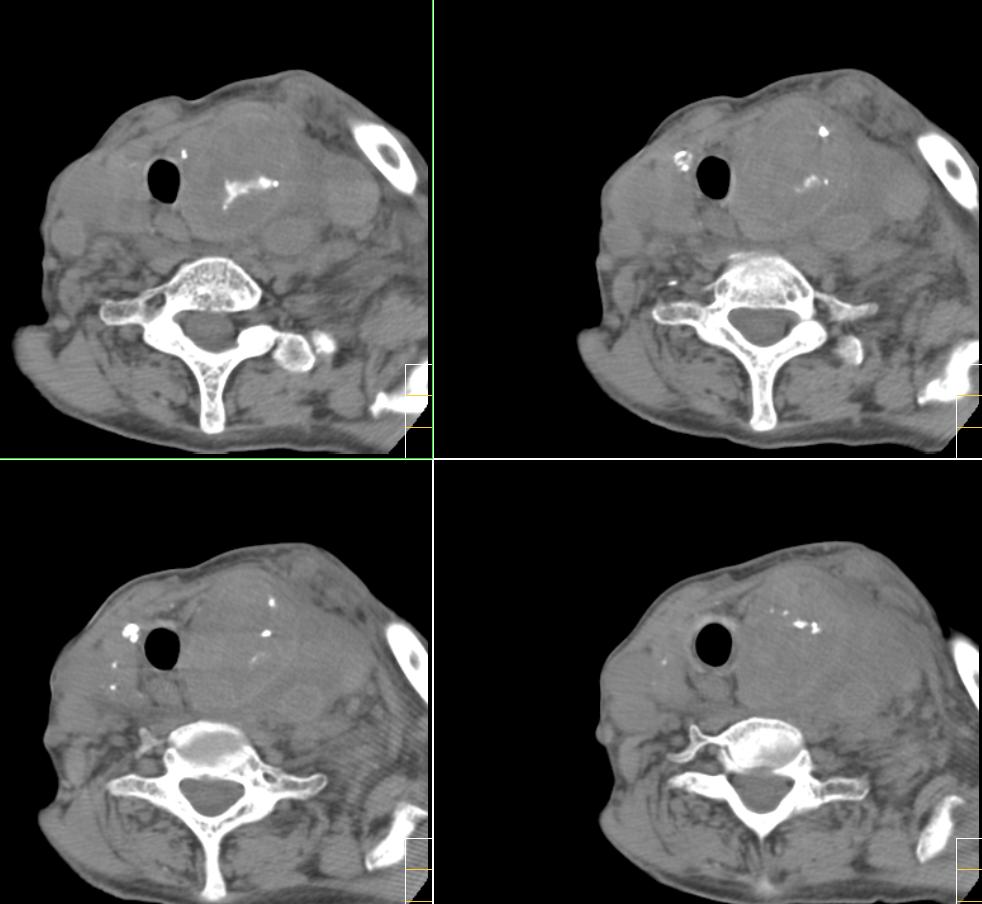

f、72y,左侧颈部发现包块及疼痛1周,彩超提示颈部血管破裂?

很遗憾,因患者高龄,高血压,肺心病、心衰,身体虚弱,未能进一步做增强扫描,临床上穿刺为动脉血,考虑颈动脉血管破裂(我觉得气体影不好解释),家属放弃治疗出院。[emb10]

考虑左侧甲状腺癌破坏气管,并颈部积气、淋巴结肿大。